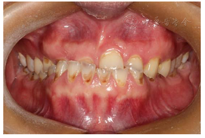

(1)面部检查:面部外形不对称,颏部居中,两侧口角高度不一致,面下1/3高度减小,两侧颧弓突度一致,下颌前突。中位笑线,上唇长度适中(图1)。(2)关节检查:颞颌关节:弹响(-),杂音(-),疼痛(-)。开口度正常,开口型有偏斜,肌肉触诊压痛:右侧上颌结节(+)、左侧上颌结节(++)、双侧翼内肌(+),其他肌肉及颞下颌关节区未诉异常,关节载荷实验无任何紧张和疼痛不适。(3)口内检查:上下颌牙中线较面中线向右偏斜,前后牙广泛不均匀磨耗,前牙磨耗后呈刃状;14、21、22、23及下颌牙唇颊侧颈部见釉质缺损,部分牙本质暴露,呈黄褐色,少量白垩色;44牙见开髓孔,表面暂封。12缺失,缺失牙间隙无。全口牙龈色形质未见异常,11牙、21牙唇侧牙龈龈缘高度不一致,21牙较11牙龈缘高约3mm。全口口腔卫生状况良好,菌斑、软垢少量,未及牙石及牙周袋。咬合检查:11-14牙与对颌牙反

,21牙与31、31牙对刃,左侧尖牙至前磨牙深覆盖,

曲线不平(图2,图3)。(4)影像学检查: